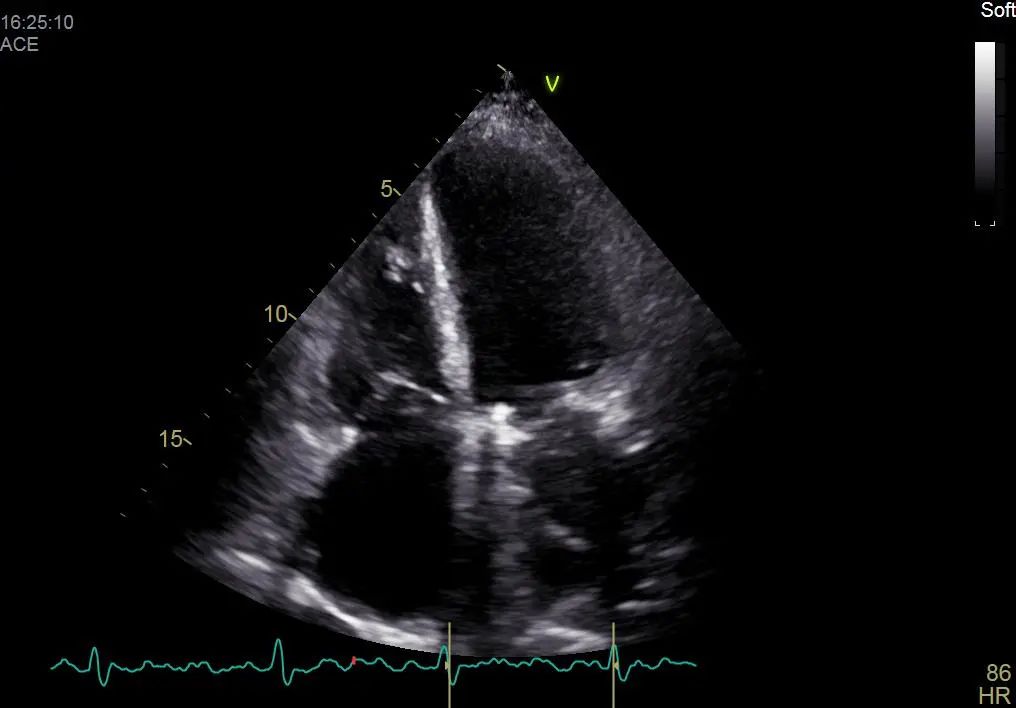

患者自述于其他医院诊断为扩张型心肌病,为进一步确认病情,吉心影像科医生为于女士进行了细致的检查。患者心电图结果显示心律失常,心房颤动,心脏彩超结果显示全心增大,二尖瓣回声增强增厚,瓣叶开放略受限,瓣叶关闭对合不良,三尖瓣开放幅度正常,关闭对合不良,左室及右室运动幅度减低。心脏超声结果显示二尖瓣关闭不全、三尖瓣关闭不全、左室收缩及舒张功能减低,右室收缩及舒张功能减低。

术前彩超影像